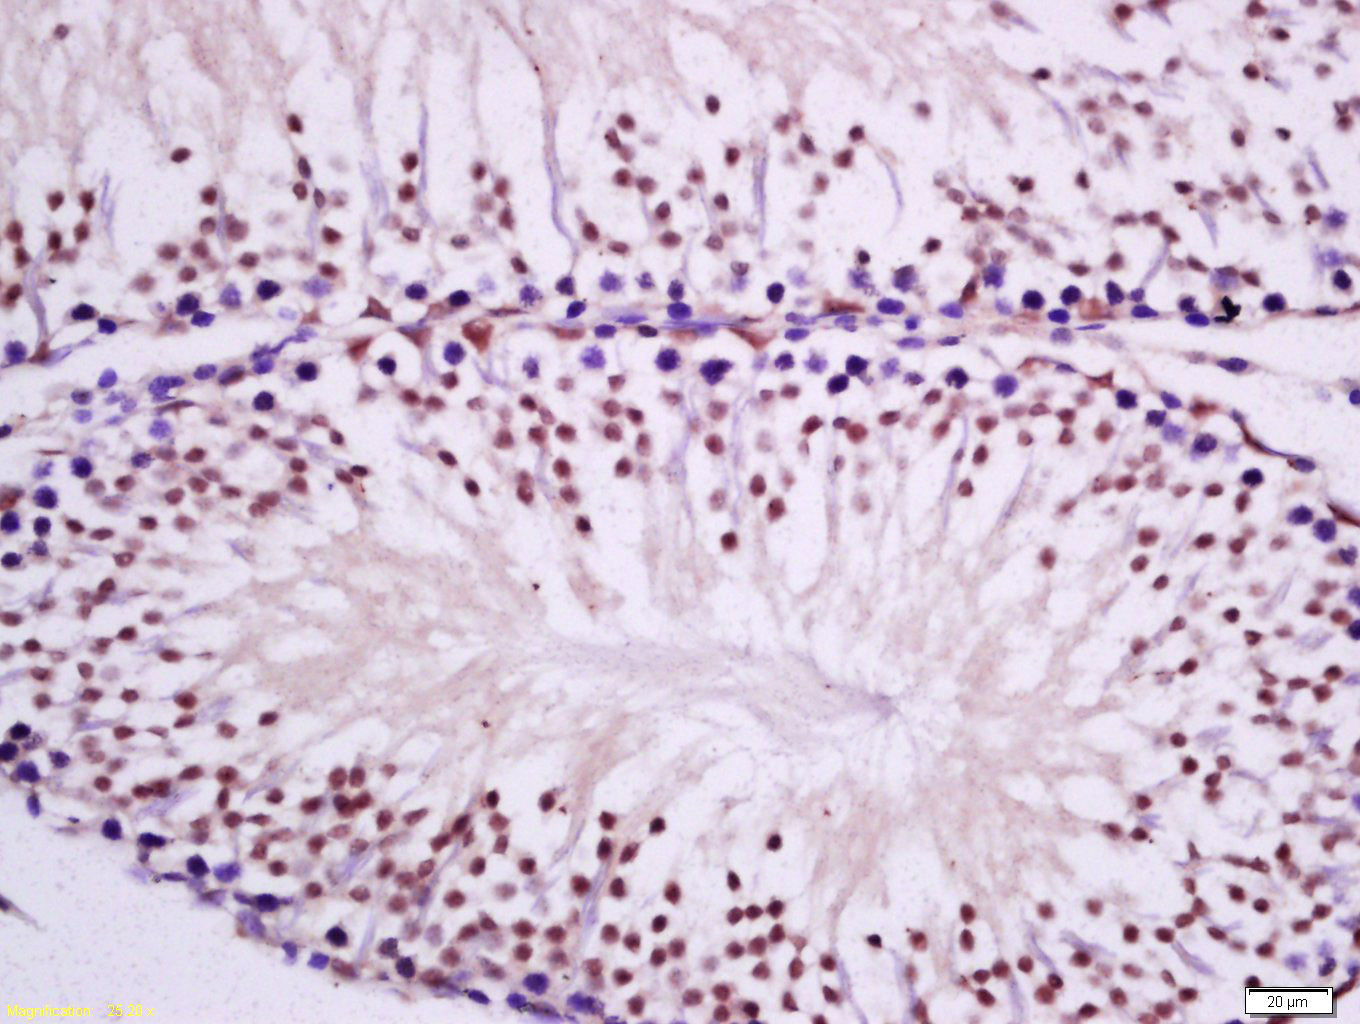

Tissue/cell: human kidney tissue; 4% Paraformaldehyde-fixed and paraffin-embedded; Antigen retrieval: citrate buffer ( 0.01M, pH 6.0 ), Boiling bathing for 15min; Block endogenous peroxidase by 3% Hydrogen peroxide for 30min; Blocking buffer (normal goat serum,C-0005) at 37℃ for 20 min; Incubation: Anti-PKC epsilon Polyclonal Antibody, Unconjugated(bs-2329R) 1:200, overnight at 4°C, followed by conjugation to the secondary antibody(SP-0023) and DAB(C-0010) staining